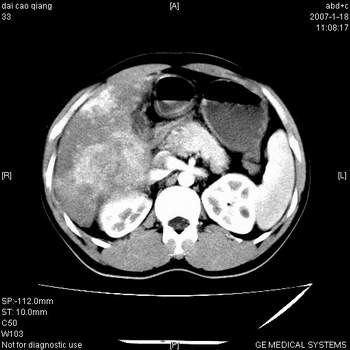

3、并可见门静脉右支癌栓形成

5、腹主动脉旁结节影,考虑肿大淋巴结。

肝右叶巨大不均匀低密度肿块,前缘有假包膜,增强明显的呈快进快出表现,门脉右支有癌栓,病人虽然年轻但还是首先考虑肝右叶巨块形肝癌,病人血象高只能说有合并感染。不支持肝脓肿。

巨块型肝癌并门静脉右支癌栓

肝右叶巨块型肝癌破裂、门脉瘤栓形成。